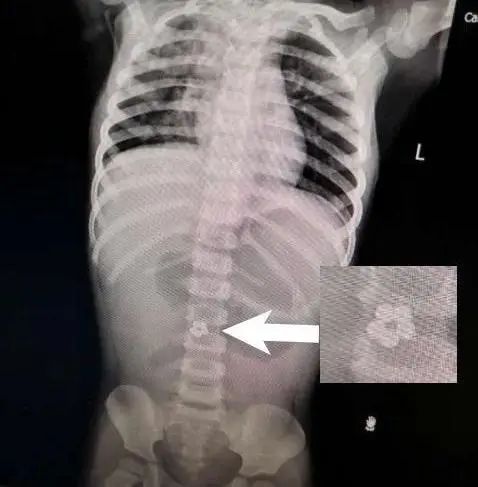

X光检查发现,小静腹中有5颗小球

居然在小静肚子里发现,有5个连成圈的小球!

打开腹腔后,医生终于找到了磁力球排不出来的原因:这5个小球分布在不同的肠段,但却牢牢地吸在一起。

医生小心地取出小磁球,再把穿孔的肠道切除,最后进行了缝合。整个手术足足花了2个小时。